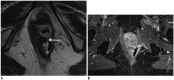

Although a rare disease, anal cancer is increasingly being diagnosed in patients with risk factors, mainly anal infection with the human papilloma virus. Magnetic resonance imaging (MRI) with external phased-array coils is recommended as the imaging modality of choice to grade anal cancers and to evaluate the response assessment after chemoradiotherapy, with a high contrast and good anatomic resolution of the anal canal. MRI provides a performant evaluation of size, extent and signal characteristics of the anal tumor before and after treatment, as well as lymph node involvement and extension to the adjacent organs. MRI is also particularly helpful in the assessment of complications after treatment, and in the diagnosis for relapse of the diseases.